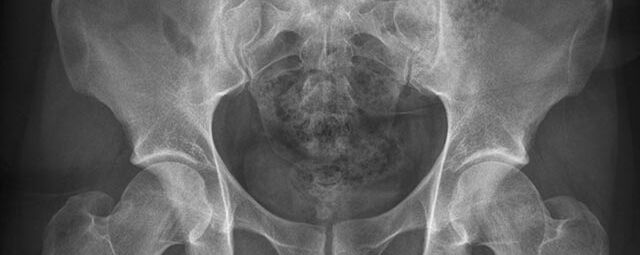

Konventionelles Röntgen

Der Begriff Röntgen, oder auch Röntgendiagnostik bezeichnet ein Verfahren in der Radiologie, bei dem von einer Röntgenröhre elektromagnetische Wellen (Röntgenstrahlen) durch die zu untersuchende Körperregion des Patienten gesendet werden. Je nach Dichte der Gewebeart des Körpers (z.B. Knochen oder Lunge) werden die Röntgenstrahlen im Körper unterschiedlich stark abgeschwächt. Ein digitaler Detektor empfängt dann die Röntgenstrahlen, die in abgeschwächter Form den Körper wieder verlassen haben. Daraus wird das Röntgenbild erzeugt.

Die Röntgenuntersuchung ist weiterhin eine unverzichtbare Basisdiagnostik. Viele Fragen können in der medizinischen Diagnostik mit einer konventionellen Röntgenaufnahme geklärt werden.

Durch den Einsatz neuester volldigitaler Röntgentechnik wird die Strahlendosis auf niedrigstem Niveau gehalten.

Röntgen Knochen

• Fraktur

• Arthrose

• Rheumatische Gelenkerkrankungen

• Degenerative Veränderungen der Wirbelsäule

• Knochentumor

• Osteoporose

• Therapiekontrolle nach OP am Skelettsystem

• Vollautomatische Erstellung von Ganzbein- und Ganzwirbelsäulenaufnahmen